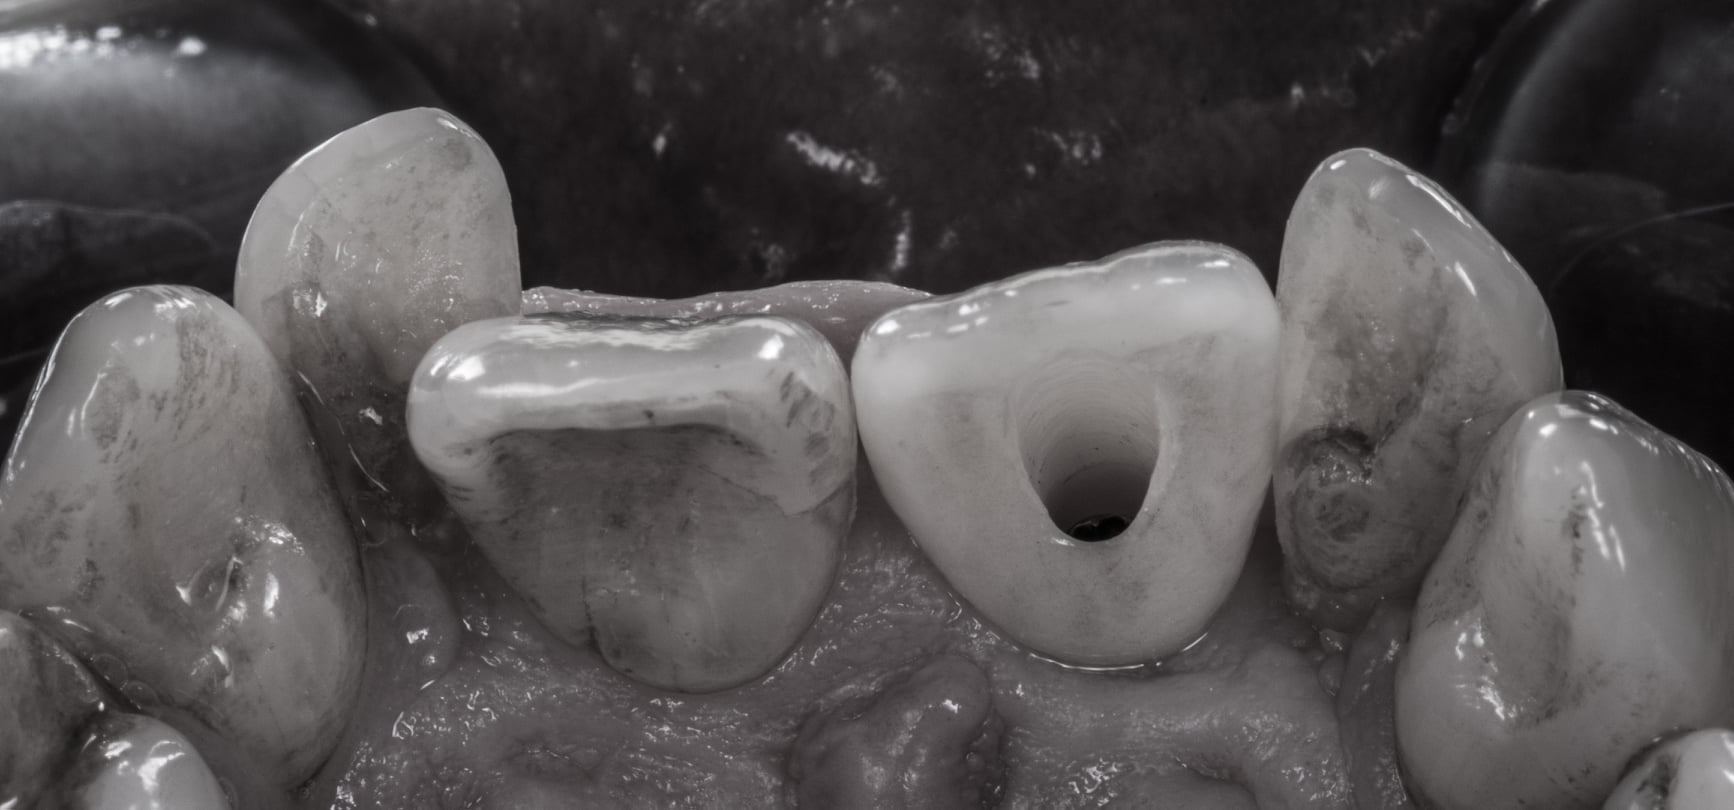

Oggi però abbiamo una soluzione che ci permette di consegnare questa corona avvitata al nostro paziente portando il foro di emergenza del canale di avvitamento dalla parte palatale. Lì potrà essere agevolmente chiuso in composito senza compromessi estetici.

Ecco quindi che l’unico motivo che poteva giustificare una protesi cementata su impianti viene miseramente a cadere!!